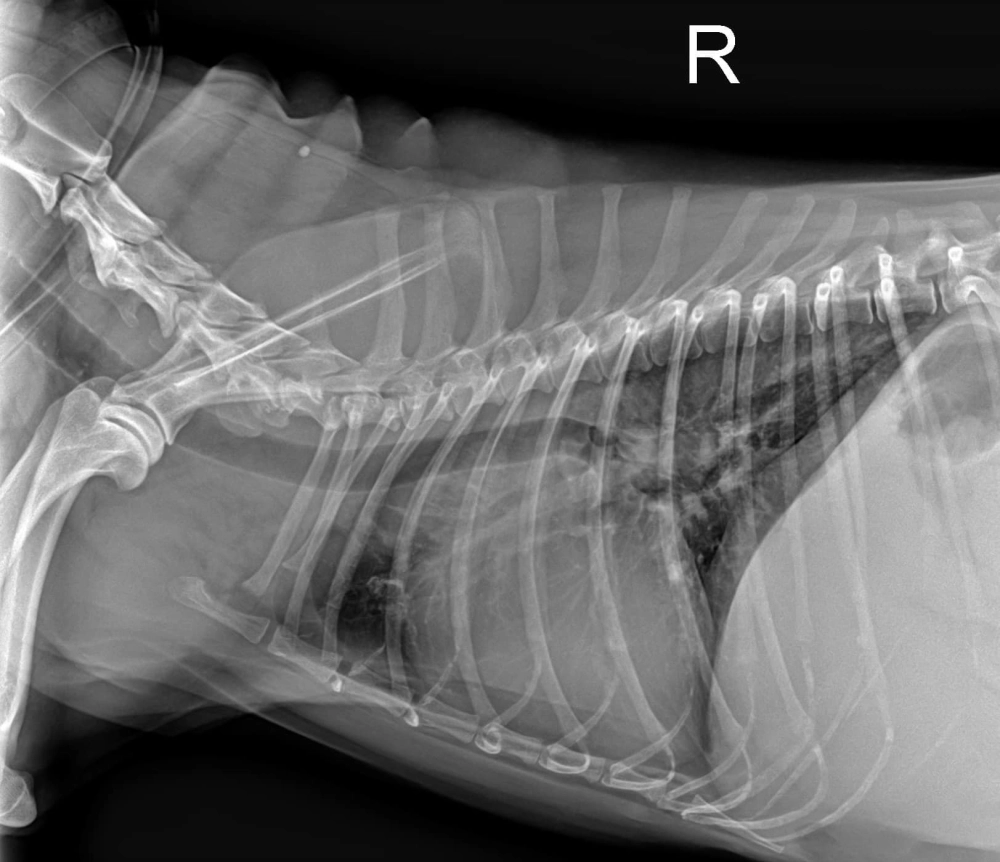

🩻第二步: X光檢查,心臟輪廓變大(VHS=11.0);肺葉呈現肺泡型病徵(alveolar pattern)。

X光,心臟輪廓明顯變大